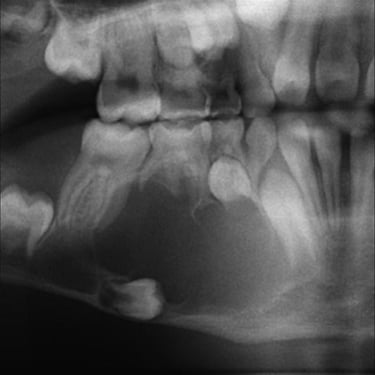

Quiste odontogénico

Un quiste odontogénico es una lesión benigna que se desarrolla en los tejidos asociados con el desarrollo dental.

Los pacientes pueden experimentar hinchazón, dolor y movilidad dental.

El tratamiento incluye la extirpación quirúrgica del quiste y la evaluación para evitar recurrencias.